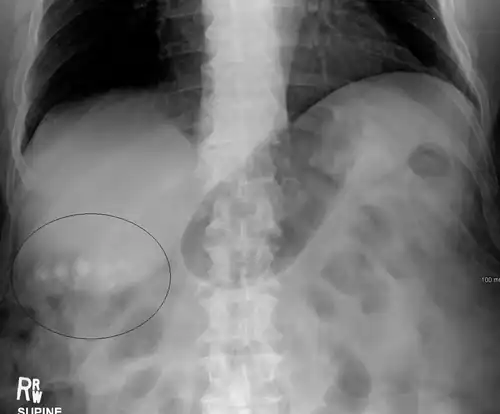

On abdominal ultrasound, sinking gallstones usually have posterior acoustic shadowing. In floating gallstones, reverberation echoes (or comet-tail artifact) is seen instead in a clinical condition called adenomyomatosis. Another sign is wall-echo-shadow (WES) triad (or double-arc shadow) which is also characteristic of gallstones.[43]

-

A 1.9 cm gallstone impacted in the neck of the gallbladder and leading to cholecystitis as seen on ultrasound. There is 4 mm gall bladder wall thickening.

Gallstones as seen on plain X-ray